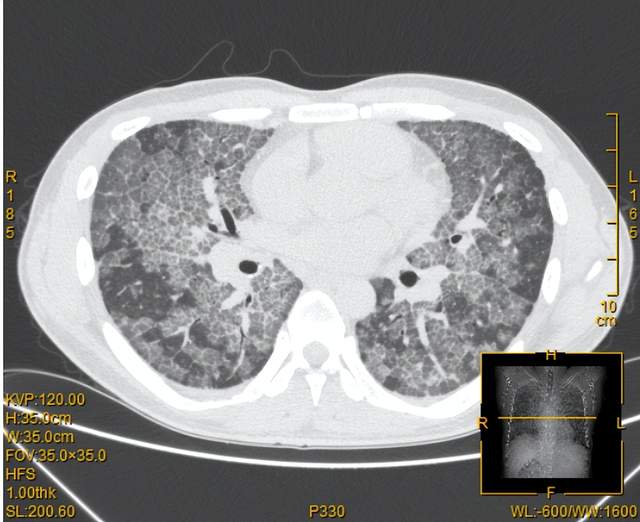

(胸部CT呈“铺路石征”)

肺泡蛋白沉积症是一种罕见的肺部弥漫性疾病,病因未明,发病率约为百万分之三点七。其主要原因是肺泡巨噬细胞功能失调致表面活性蛋白和脂质沉积于肺泡内,临床表现主要为进行性气促、低氧血症、咳“牛奶”样泡沫痰,部分患者无任何症状,仅为体检时意外发现。